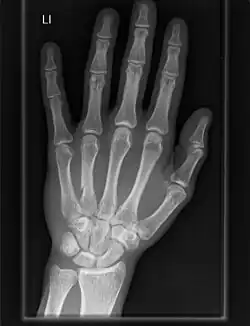

The carpometacarpal (CMC) joints are five joints in the wrist that articulate the distal row of carpal bones and the proximal bases of the five metacarpal bones.

The CMC joint of the thumb or the first CMC joint, also known as the trapeziometacarpal (TMC) joint, differs significantly from the other four CMC joints and is therefore described separately.

- The second metacarpal articulates primarily with the trapezoid and secondarily with the trapezium and capitate.

- The third metacarpal articulates primarily with the capitate,

- The fourth metacarpal articulates with the capitate and hamate.

- The fifth metacarpal articulates with the hamate.